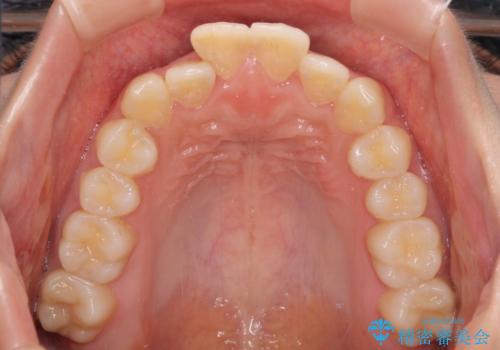

- 口元の閉じにくさを気にして来院された患者様です。

上下ともに歯列が前方に突出していたため、上下左右の第一小臼歯4本を抜去し、ワイヤー装置による矯正治療を行うこととしました。

舌の突出癖による影響もあったため、舌のトレーニングを並行して実施しました。